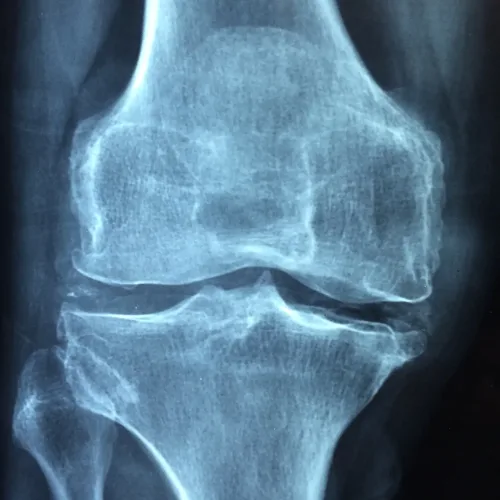

Osteoarthritis is a type of arthritis where the bone, cartilage and synovium wear down, leading to pain and stiffness. Synovium lines the joints and produces synovial fluid that lubricates the joins as well as supplies them with nutrients and oxygen. A 2016 study from the American Journal of Translational Research compared the effectiveness of acupuncture and physiotherapy for treating knee osteoarthritis. When looking at motor scores, pain, stiffness and physical function, those patients who received acupuncture had significantly improved scores compared to patients who received physiotherapy.

- Knee arthritis